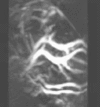

Thermoacoustic imaging was originally proposed by Theodore Bowen in 1981 as a strategy for studying the absorption properties of human tissue using virtually any kind of electromagnetic radiation.[1] But Alexander Graham Bell first reported the physical principle upon which thermoacoustic imaging is based a century earlier.[2] He observed that audible sound could be created by illuminating an intermittent beam of sunlight onto a rubber sheet. Shortly after Bowen's work was published, other researchers proposed methodology for thermoacoustic imaging using microwaves.[3] In 1994 researchers used an infrared laser to produce the first thermoacoustic images of near-infrared optical absorption in a tissue-mimicking phantom, albeit in two dimensions (2D).[4] In 1995 other researchers formulated a general reconstruction algorithm by which 2D thermoacoustic images could be computed from their "projections," i.e. thermoacoustic computed tomography (TCT).[5] By 1998 researchers at Indiana University Medical Center extended TCT to 3D and employed pulsed microwaves to produce the first fully three-dimensional (3D) thermoacoustic images of biologic tissue [an excised lamb kidney (Fig. 1)].[6] The following year they created the first fully 3D thermoaocustic images of cancer in the human breast, again using pulsed microwaves (Fig. 2).[7] Since that time, thermoacoustic imaging has gained widespread popularity in research institutions worldwide.[8] As of 2008, three companies were developing commercial thermoacoustic imaging systems - Seno Medical, Endra, Inc. and OptoSonics, Inc.

- ↑ Kruger RA, Miller KD, Reynolds HE, Kiser Jr WL, Reinecke DR, Kruger GA. Contrast enhancement of breast cancer in vivo using thermoacoustic CT at 434 MHz. Radiology 2000;216: 279-283.